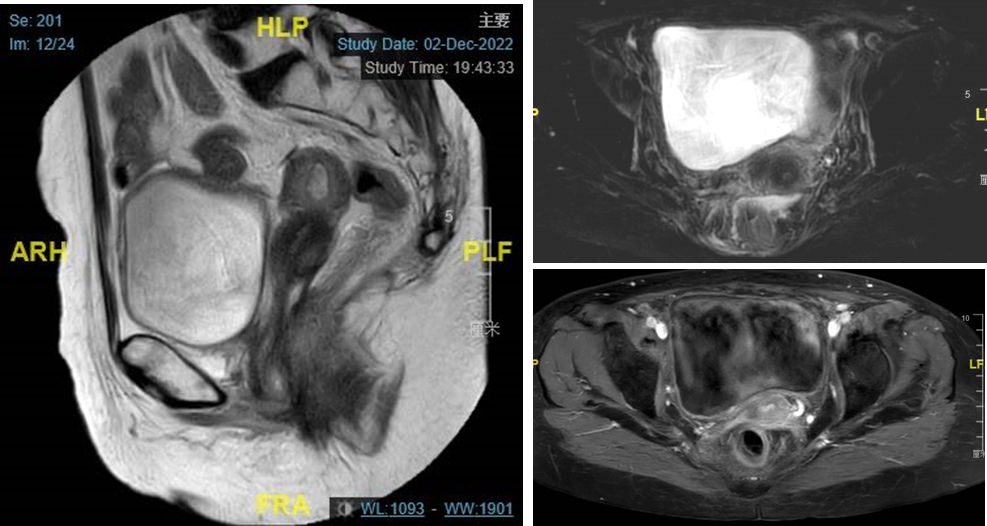

CT检查:宫颈见不均匀强化肿块影,约2.92*4.21cm,阴道后壁肿块约4.56*4.35cm,病灶与宫颈后唇分界不清。

图1. CT提示宫颈占位,见不均匀强化肿块影,约2.92*4.21cm,阴道后壁肿块约4.56*4.35cm,病灶与宫颈后唇分界不清。颈、胸部未见异常

盆腔MRI检查:阴道后壁肿瘤约4.6*1.6*4.7cm,病灶与宫颈后唇分界不清,局部与直肠前壁分界不清。肿块最外缘距左侧盆壁约2cm,下缘距阴道外口约2.9cm,增强后明显强化。

图2. 盆腔MRI提示阴道后壁肿瘤约4.6*1.6*4.7cm,病灶与宫颈后唇分界不清,局部与直肠前壁分界不清